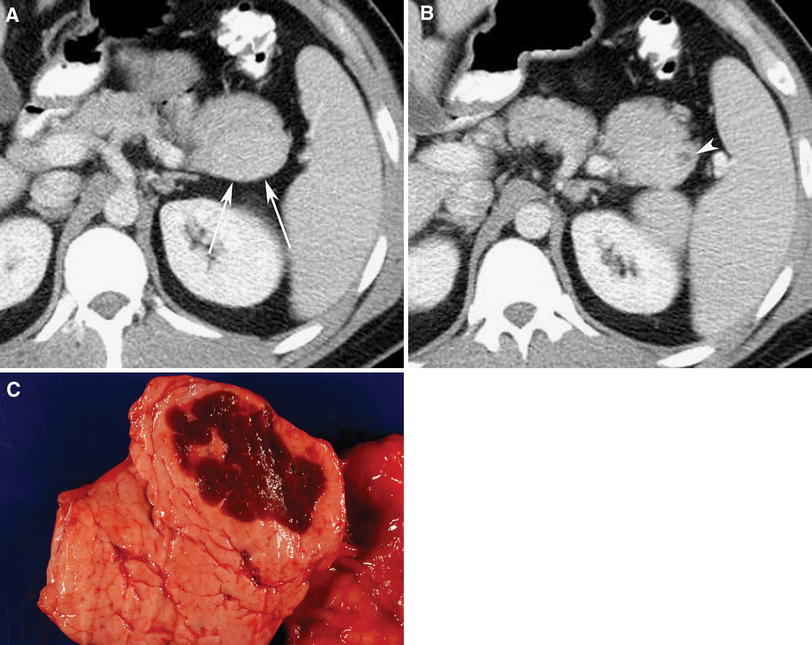

MediaObjects/261_2011_9830_Fig3_HTML.jpg

Fig. 3 27-Year-old man with history of abdominal discomfort, and mass was found in the tail of the pancreas on CT performed at another institution. A and B Venous phase axial CT images show solid mass (4.1 cm) in the tail of the pancreas, which is isodense to spleen. Small cystic component (arrowhead) is seen in periphery of mass. Neuroendocrine neoplasm was suspected, and patient underwent distal pancreatectomy and splenectomy. Pathology revealed IPAS with associated dilated pancreatic duct. C Image of gross specimen shows heterotopic spleen in tail of pancreas.